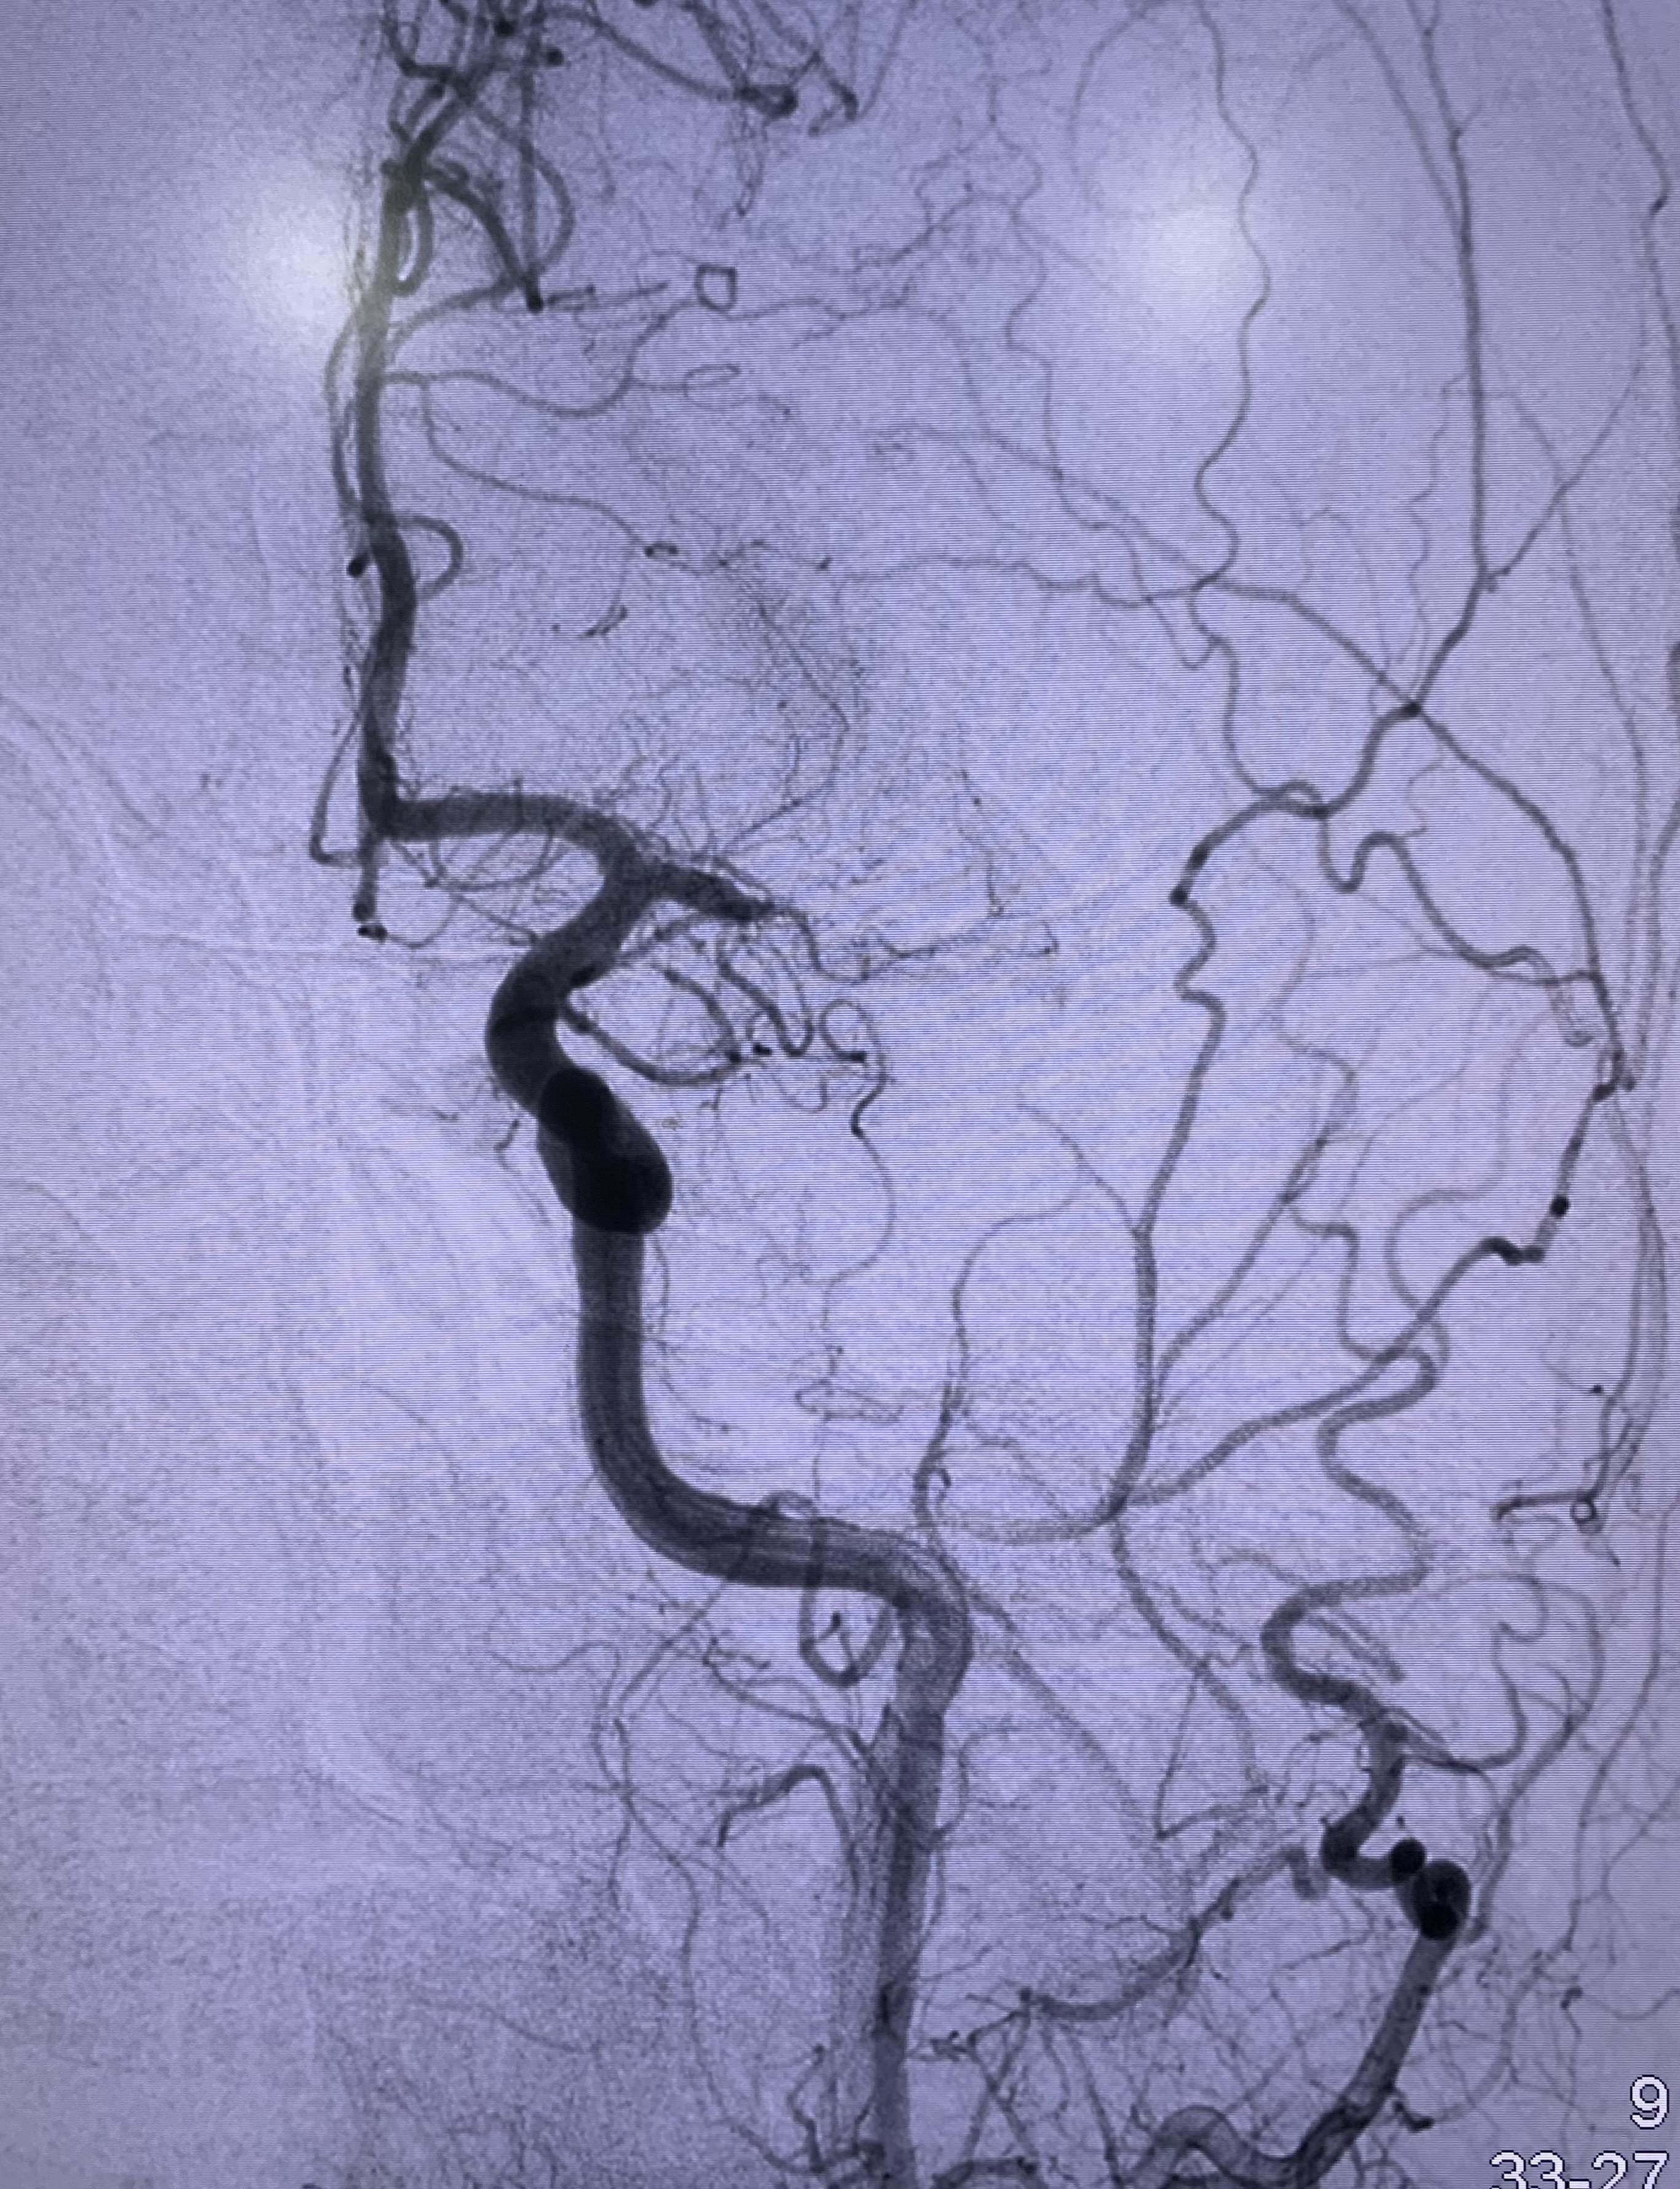

Promptly after admission, the patient received immediate treatment through intravenous thrombolysis with a dosage of 30 mg of tenecteplase. Subsequently, a mechanical thrombectomy procedure was conducted, employing a RED 72 reperfusion catheter (Penumbra). Following 2 passes of the catheter, a resilient clot was successfully retrieved. This intervention resulted in the complete recanalization of the MCA, leading to full perfusion of the entire left MCA territory (modified treatment in cerebral infarction score of 3, a successful recanalization). Notably, during digital subtraction angiography, an incidental finding revealed a shelf-like filling defect within the left carotid bulb, which was subsequently identified as a carotid web (Figures 3, 4, and 5).